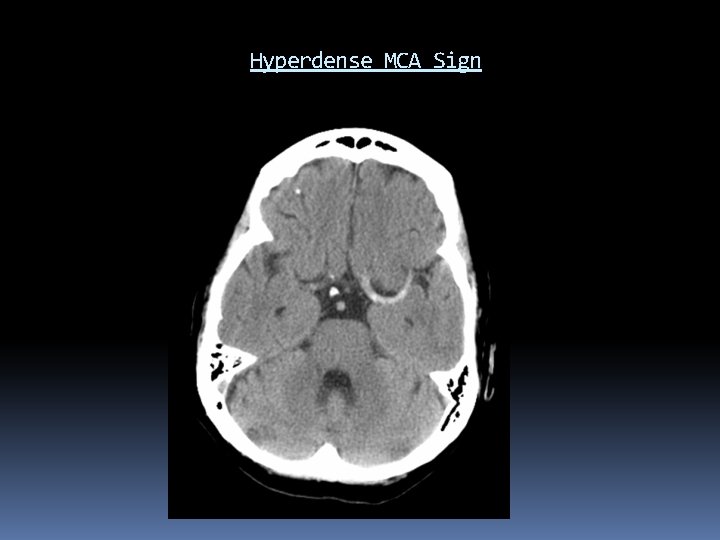

Acute Ischemic Stroke Work Up Labs: CBC with platelets, CMP, PTT, cardiac biomarkers, EKG. Imaging: Emergent non-contrast CT Distinguishes hemorrhagic from ischemic stroke Defines age and anatomic distribution of stroke Large hypodense area seen within 3 hours brings into question of timing of AIS and may predict poor outcome Hyperdense MCA sign, insular ribbon sign, obscuration of lentiform nucleus, loss of gray-white junction

Hyperdense MCA Sign